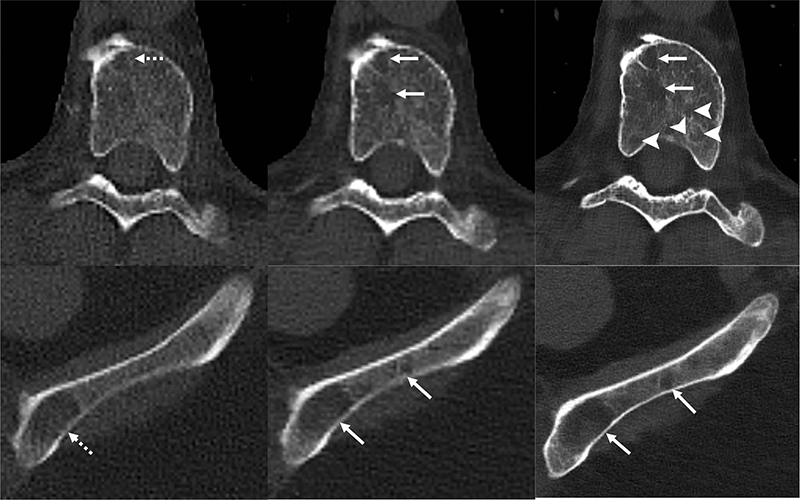

Images in a 71-year-old man with multiple myeloma. Lytic lesions (dashed arrows) within a thoracic vertebral body and the left iliac wing are more conspicuous on the noncontrast-enhanced axial photon-counting detector (PCD) CT image (middle; solid arrows) compared with noncontrast-enhanced axial energy-integrating detector CT image (left). With 0.6-mm Br76 noncontrast-enhanced axial PCD CT reconstruction images (right), more lesions were detected (arrowheads).